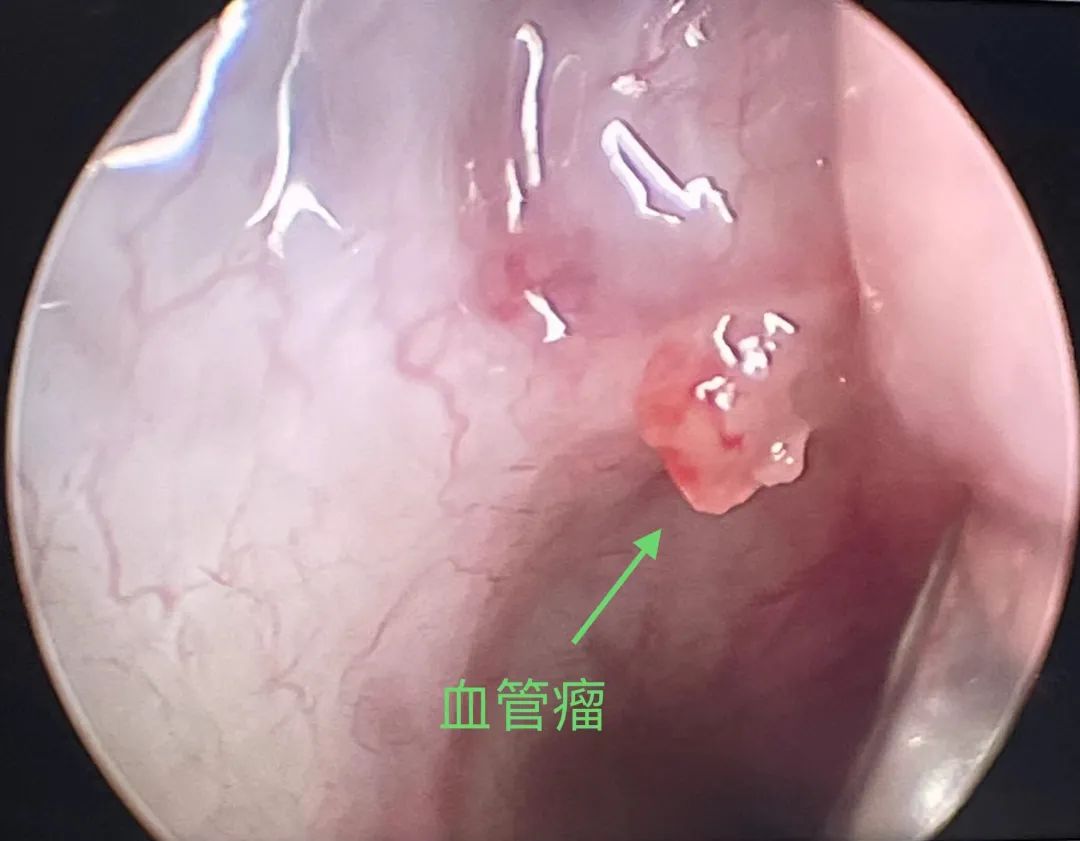

张治军主任在手术中发现,林先生鼻中隔右侧前中部高位偏曲明显,鼻黏膜肿胀,有少许伪膜,右侧鼻腔显著狭窄,嗅裂、中鼻道及上鼻道难以显露。没有视野,情况很难明确。他直接在术中为林先生矫正鼻中隔,视野终于豁然开朗。推移中鼻甲,仔细查看嗅裂与中鼻道,终于找到了出血点:右侧中鼻道后部穹窿处的黏膜表面,有一处局限性粟粒状突起,轻触即可见搏动性出血!张治军主任立即对出血点予以双极电凝,为林先生止住了鼻血!